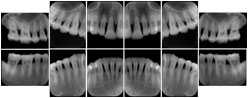

2. A patient requests cosmetic surgery to enhance their facial appearance. The case requires consultation between an orthodontist in New York and an oral surgeon in California. The cephalometric series of 2D projections constructed from the volumetric CT data that is used for the discussion is arranged by a Structured Display for transfer between the two practitioners.

Cephalometric Series Structured Display

Figure OO-2. Cephalometric Series Structured Display